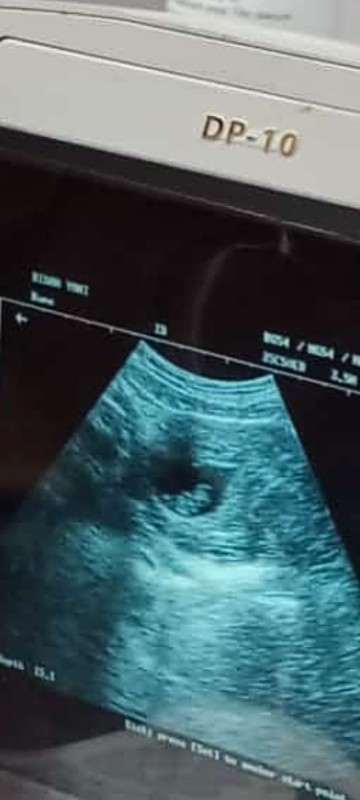

Bunda saya ingin bertanya kehamilan 10minggu usg masih kantongnya aja janinnya belum ada normal kah

maaf Bun itu gsnya udh besar bgt, seharusnya udh ada janin.